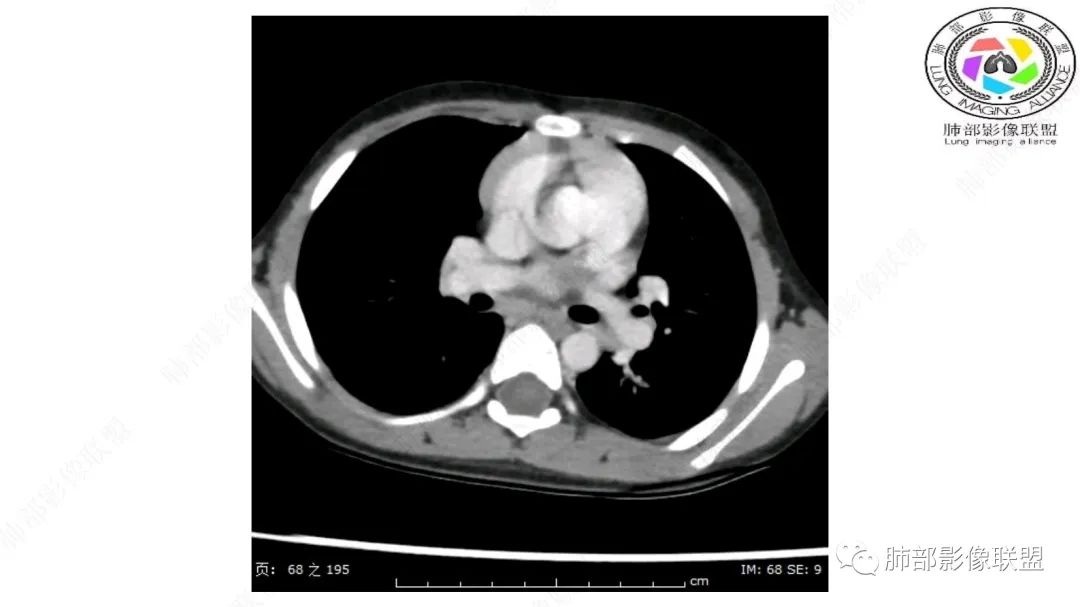

右上纵隔混杂密度肿块,边缘光整,与纵隔分界清,其内多发脂肪密度,增强无明显强化,其内血管穿行,考虑纵隔脂肪母细胞瘤,鉴别畸胎瘤,脂肪肉瘤。

右纵隔团状,密度不均,脂肪密度为主,内可见腺体样组织,类似乳腺,病灶边缘有分叶,与胸腺关系密切,增强后血管穿行。考虑胸腺脂肪瘤(不典型垂乳征),鉴别畸胎瘤。

三岁小儿,右侧纵隔巨大脂肪密度肿块,肺动脉穿行其中,密度欠均匀,未见明确实性成分,纵隔脂肪母细胞瘤,冬眠瘤鉴别纵隔脂肪增多症(多弥漫对称)。

可以看到造影剂进入的丛状结构

密度不均,非纯脂肪成分。斑片状密度略高区域有轻度填充式强化。

婴幼儿,病变较大,跨肺门,分叶,富含纤维或黏液、含成熟脂肪,破坏力弱或无,浸润性生长模式不明显,未见远处转移。

综合:富含成熟脂肪的、可以有丛状结构的,可以有纤维或黏液的良性或低度恶性肿瘤。常见疾病谱:脂肪瘤、神经纤维瘤样错构瘤、冬眠瘤、血管脂肪瘤、髓脂肪瘤、脂肪母细胞瘤、黏液样脂肪肉瘤。

病灶属于交界区,主体位于肺内,占位效应明显,前方突入胸壁,胸腺受压变形,胸膜显示欠清楚;病灶包绕上叶肺动脉;似乎有体动脉供血。符合肺内的点:包绕上叶肺动脉分支;符合纵隔的点:前方似乎突入胸壁,与胸腺关系比较密切,但是与上腔静脉的关系提示病灶不支持纵隔来源,前纵隔的常规会将上腔静脉受压后移、外移,这是不符合的。

内部血管明显,部分病灶密度增高,单纯脂肪瘤不支持。可惜的是:没有提供CT值:是否强化?如果强化,警惕恶性;胸腺肯定不符合,胸腺会将上腔静脉朝后推移。

2.肺动脉穿行也许是肺内来源最重要支持点!

脂肪母细胞瘤由成熟程度不同的脂肪组织、纤维间隔、黏液基质、小血管丛等间质成分组成,以脂肪组织与黏液样基质为主,其影像学表现取决于上述组织成分。典型的CT和MRI表现为:前后纵隔均可发生,常见于前纵隔;肿块大小不一,直径多在3cm~7cm,密度均匀,CT值呈水样或脂肪密度,脂肪组织密度或信号为主的肿块,其内密度或信号不均匀,可见粗细不一的分隔影,且有结节、片状影,后者可呈轻中度强化;结节状肿瘤包膜完整;弥漫性者包膜不明显,常呈浸润性生长;周围结构为受压和推移改变,可有少量胸腔积液,淋巴结无增大。